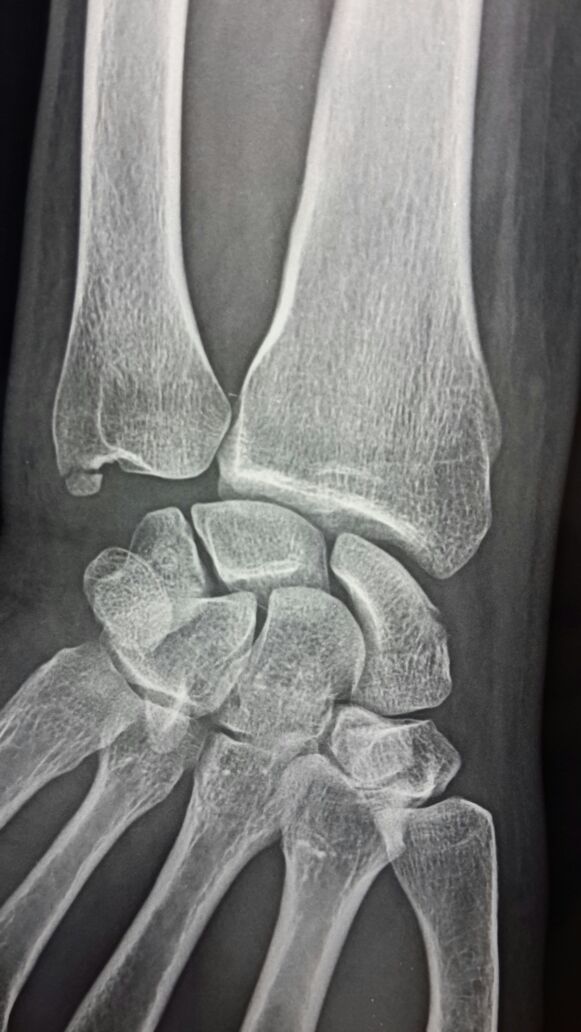

Перелом ладьевидной кости

Уважаемые коллеги, перелом ладьевидной кости и шиловидного отростка локтевой кости, возраст больного 40 лет.